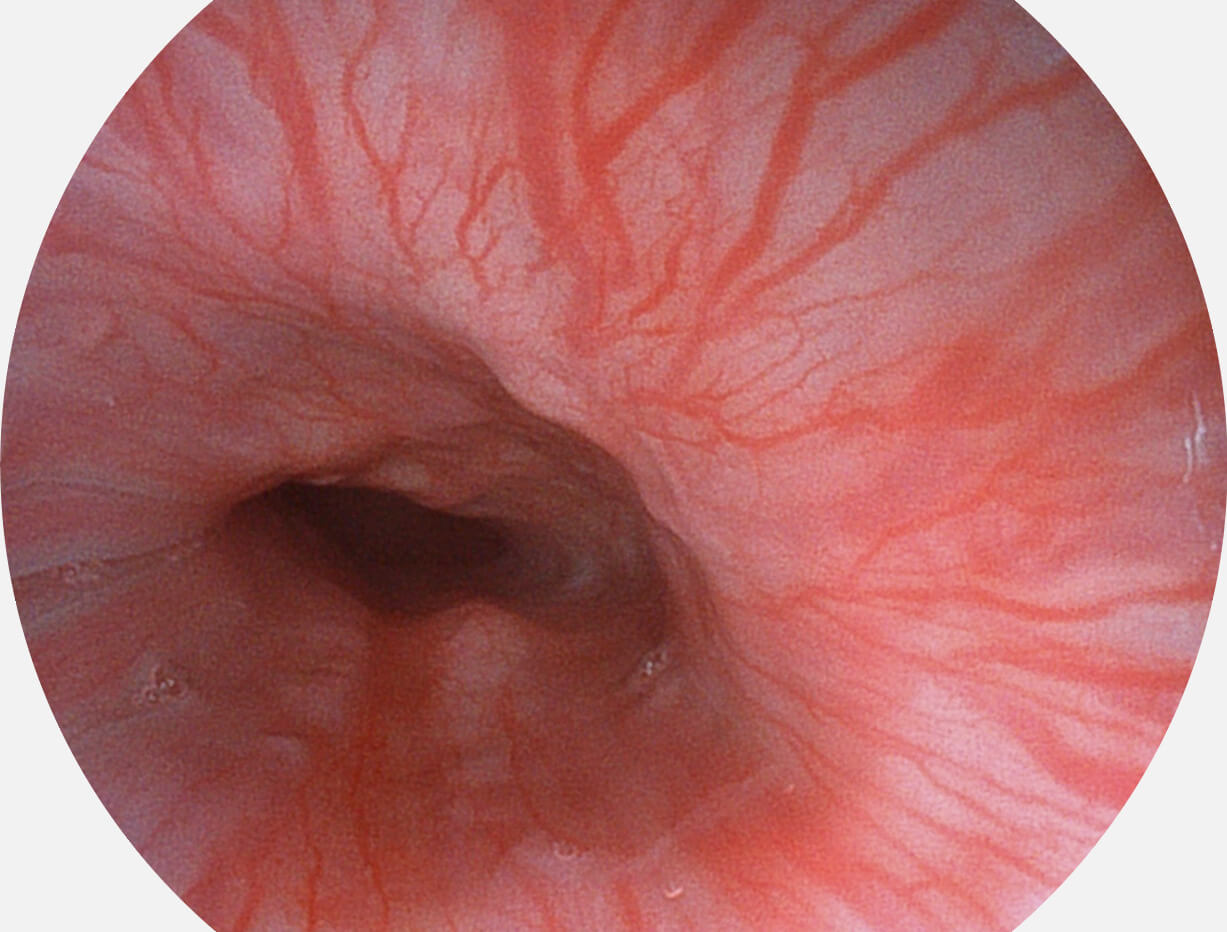

白光图像

VIST图像

强调浅层黏膜结构的同时,保证照明亮度和提升浅层微血管与中层血管颜色对比度,病变边界更清晰。